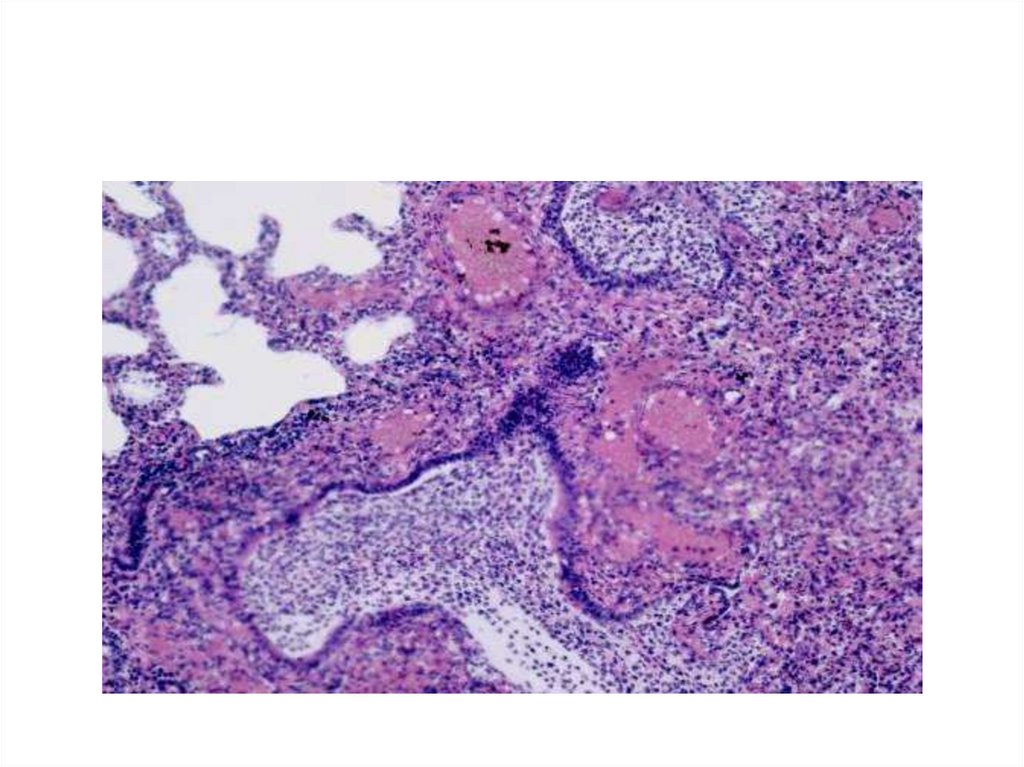

Специфическое воспаление на

примере туберкулеза:

21.

22.